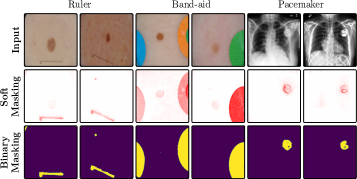

where denotes element-wise multiplication. This yields a heatmap that can be used as a soft mask or converted to a binary segmentation mask, for instance using thresholding techniques like Otsu’s method [57]. An example is shown in Fig. 2 (right), showing soft masks as heatmaps from concept-conditioned local attribution scores, along with binary masks for three known data artifacts: rulers and band-aids for skin cancer detection, and pacemakers in chest radiographs.

Notably, automated bias localization has the potential to reduce manual annotation efforts. These additional annotations can be utilized for various applications, e.g., as input for bias mitigation approaches requiring prior information on the bias to be unlearnt (see Sec. 5). Other applications include the design of metrics to measure artifact reliance or the spatial isolation of the bias to copy-paste it onto non-artifactual samples to measure the model’s sensitivity is towards the insertion of the artifact [59].

The considered datasets include ISIC2019 for melanoma detection [19, 70, 20], HyperKvasir for the identification of gastrointestinal abnormalities [10], CheXpert with chest radiographs [46], and the PTB-XL dataset [73] with 12-lead ECG (time series) data. All vision datasets contain real-world artifacts that DNNs may utilize as spurious correlation, i.e., features unrelated to the task, yet correlating with the target label. ISIC2019 is particularly known for various artifacts like colorful band-aids near benign lesions and rulers or skin markers beside malignant lesions [62, 3, 18, 59]. Moreover, HyperKvasir contains insertion tubes predominantly in samples without abnormal conditions, while CheXpert samples with cardiomegaly contain pacemakers in radiographs more frequently than in healthy patients [75]. In addition, we insert controlled artifacts into a subset of images from exactly one class per dataset. Specifically, we insert a microscope-like artifact into melanoma samples in ISIC2019. Moreover, following Dreyer et al. [28], we insert a timestamp into disease-samples from HyperKvasir, mimicking timestamps added by scanning devices. For CheXpert, we increase the brightness of radiographs with cardiomegaly, while for PTB-XL, we insert a static noise into the first second of one lead for samples with left ventricular hypertrophy (LVH). Inserting these artifacts into of samples from exactly one class creates spurious correlations for that class. Further dataset details are provided in Appendix A.4 and examples of the artifacts are shown in Fig. 5.